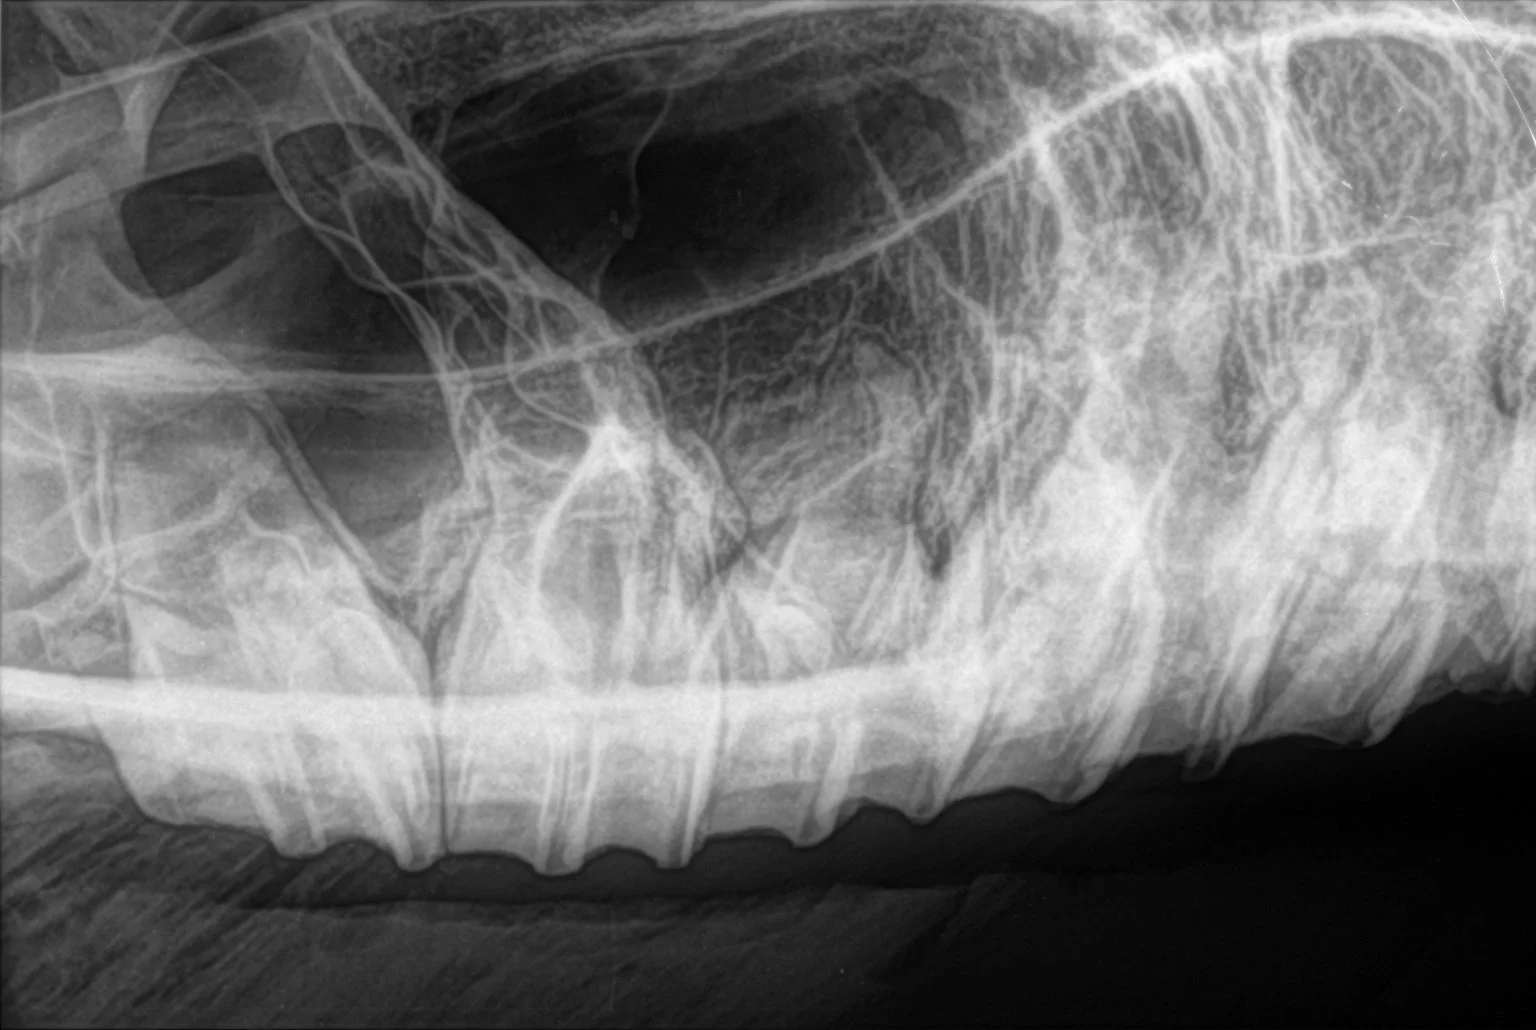

INTERVIEWER: Dr. Gieche, what constitutes a good dental examination?

DR. GIECHE: This is a subject every horse owner should have a good understanding of. Armed with this knowledge they can often tell whether the medical provider is doing a quality job or not. I routinely do two levels of examinations. The first is a very brief tactile examination of the first upper premolars (cheek teeth). This examination only provides information about the condition of these teeth. If an Oral Adjustment (OA) is not indicated here, I would proceed to a full examination of every tooth in the mouth. This requires sedation, a full mouth speculum, light source, equine dental mirror, periodontal probes, and dental explorer, to complete a visual and tactile examination of each tooth in the horse’s mouth. If the doctor does not have these tools or does not use them routinely, they are not doing a quality examination and the result is a substandard job or even injury to the horse! The first examination only tells us if an oral adjustment is needed, it does not tell us one is not needed, because only a small portion of the dentition can be evaluated this way!